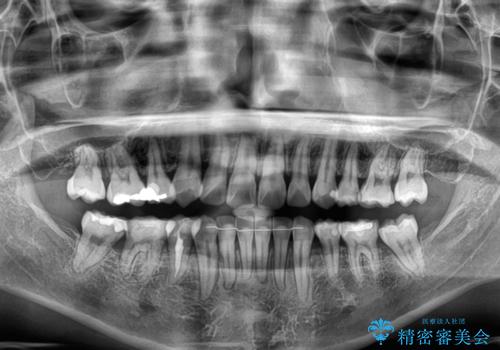

- 上下前歯の後戻りを気にして来院された患者様です。

インビザラインでの治療を希望されていて、デコボコの程度が中等度であり、安価なパッケージにて対応可能と判断されたため、インビザライン・モデレートを用いて矯正治療を行うこととしました。